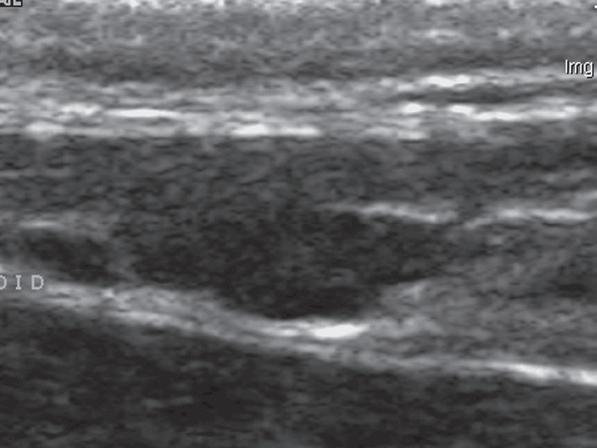

Badanie wykonano u 12-letniej, kastrowanej samicy labradora retrievera z wcześniej zdiagnozowanymi masami płucnymi i szyjnymi. W badaniu USG uwidoczniono kulisty, hipoechogeniczny guzek w obrębie prawego płata tarczycy (a). W TK masa jest nieznacznie hipodensyjna w obrazach bez wzmocnienia (b – strzałka). Lewy płat tarczycy ma prawidłową wielkość i jest hiperdensyjny (b – grot strzałki). Masa ulega umiarkowanemu wzmocnieniu po podaniu środka kontrastowego, jednak w mniejszym stopniu niż sąsiedni prawidłowy miąższ tarczycy (c – strzałka) i jej przeciwległy płat. W obrazach w rekonstrukcji grzbietowej w projekcji MIP po podaniu środka kontrastowego uwidoczniono przebieg obu tętnic szyjnych wspólnych dogrzbietowo względem płatów tarczycy (d – groty strzałek). Cieńszy przekrój MIP wykluczający tętnice szyjne ukazuje płaty tarczycy (e – strzałki) oraz lokalizację masy w obrębie prawego płata (e – grot strzałki). Biopsja wycinkowa wykazała raka tarczycy o utkaniu litym i pęcherzykowym z naciekaniem naczyń i torebki